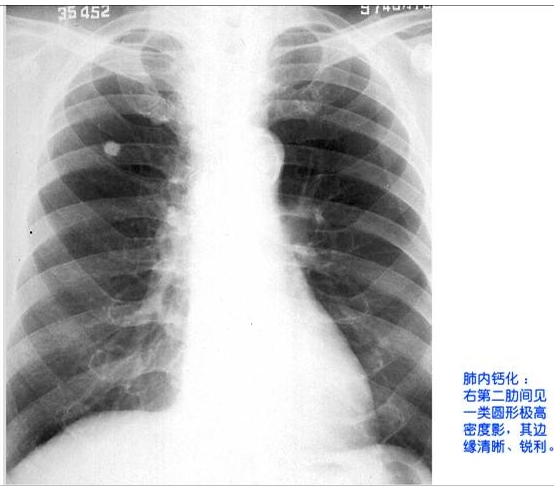

照片名称:肺内钙化